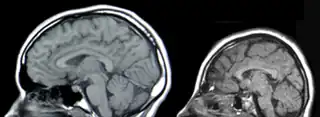

Resonancia Magnética de la Cabeza, Izquierda: Normal, Derecha:Microcefalia.